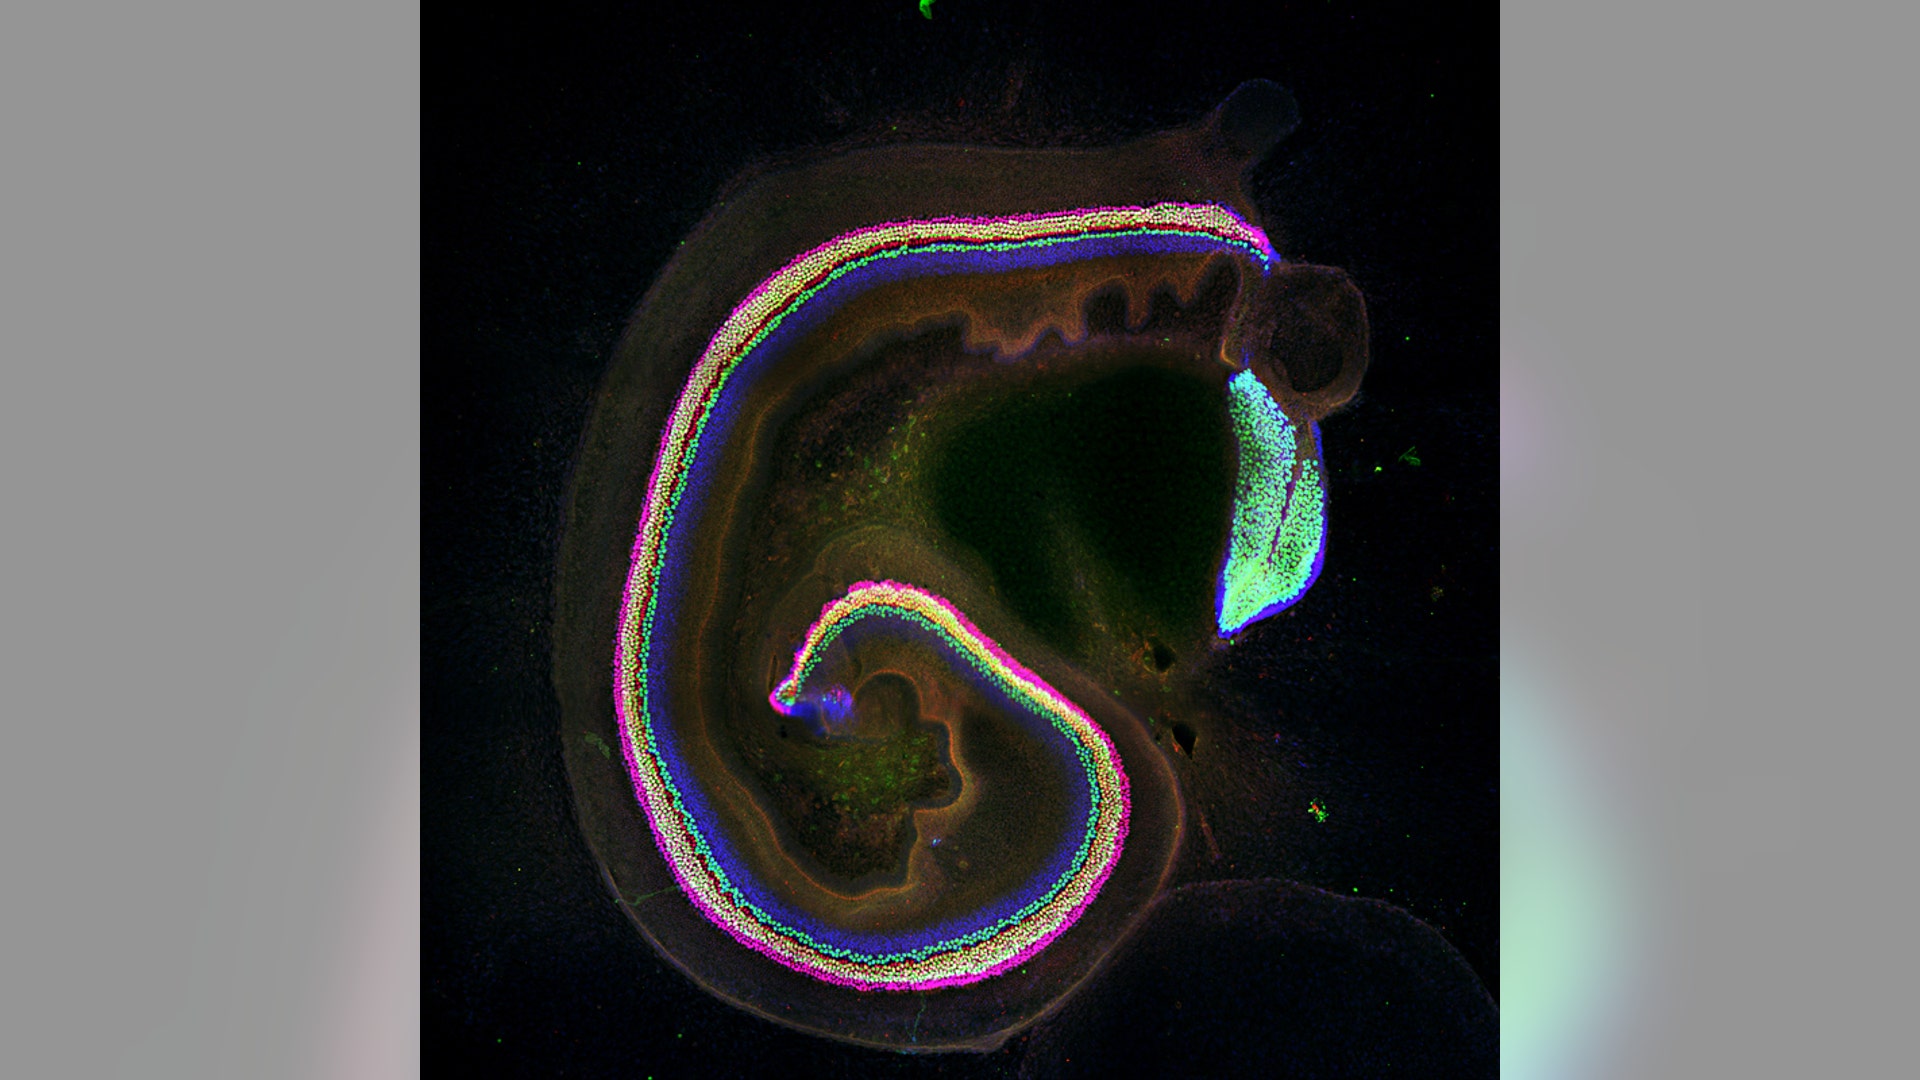

Life As You've Never Seen It: 2011's Best Microscope Photos of the Human Body

The Amazing Human Body: The mysteries of the human body have long fascinated scientists. In this gallery, find amazing images taken from the human body, as well as images from research focusing on improving the health of humans, showcased at Nikon's annual Small World Photomicrography Competition.